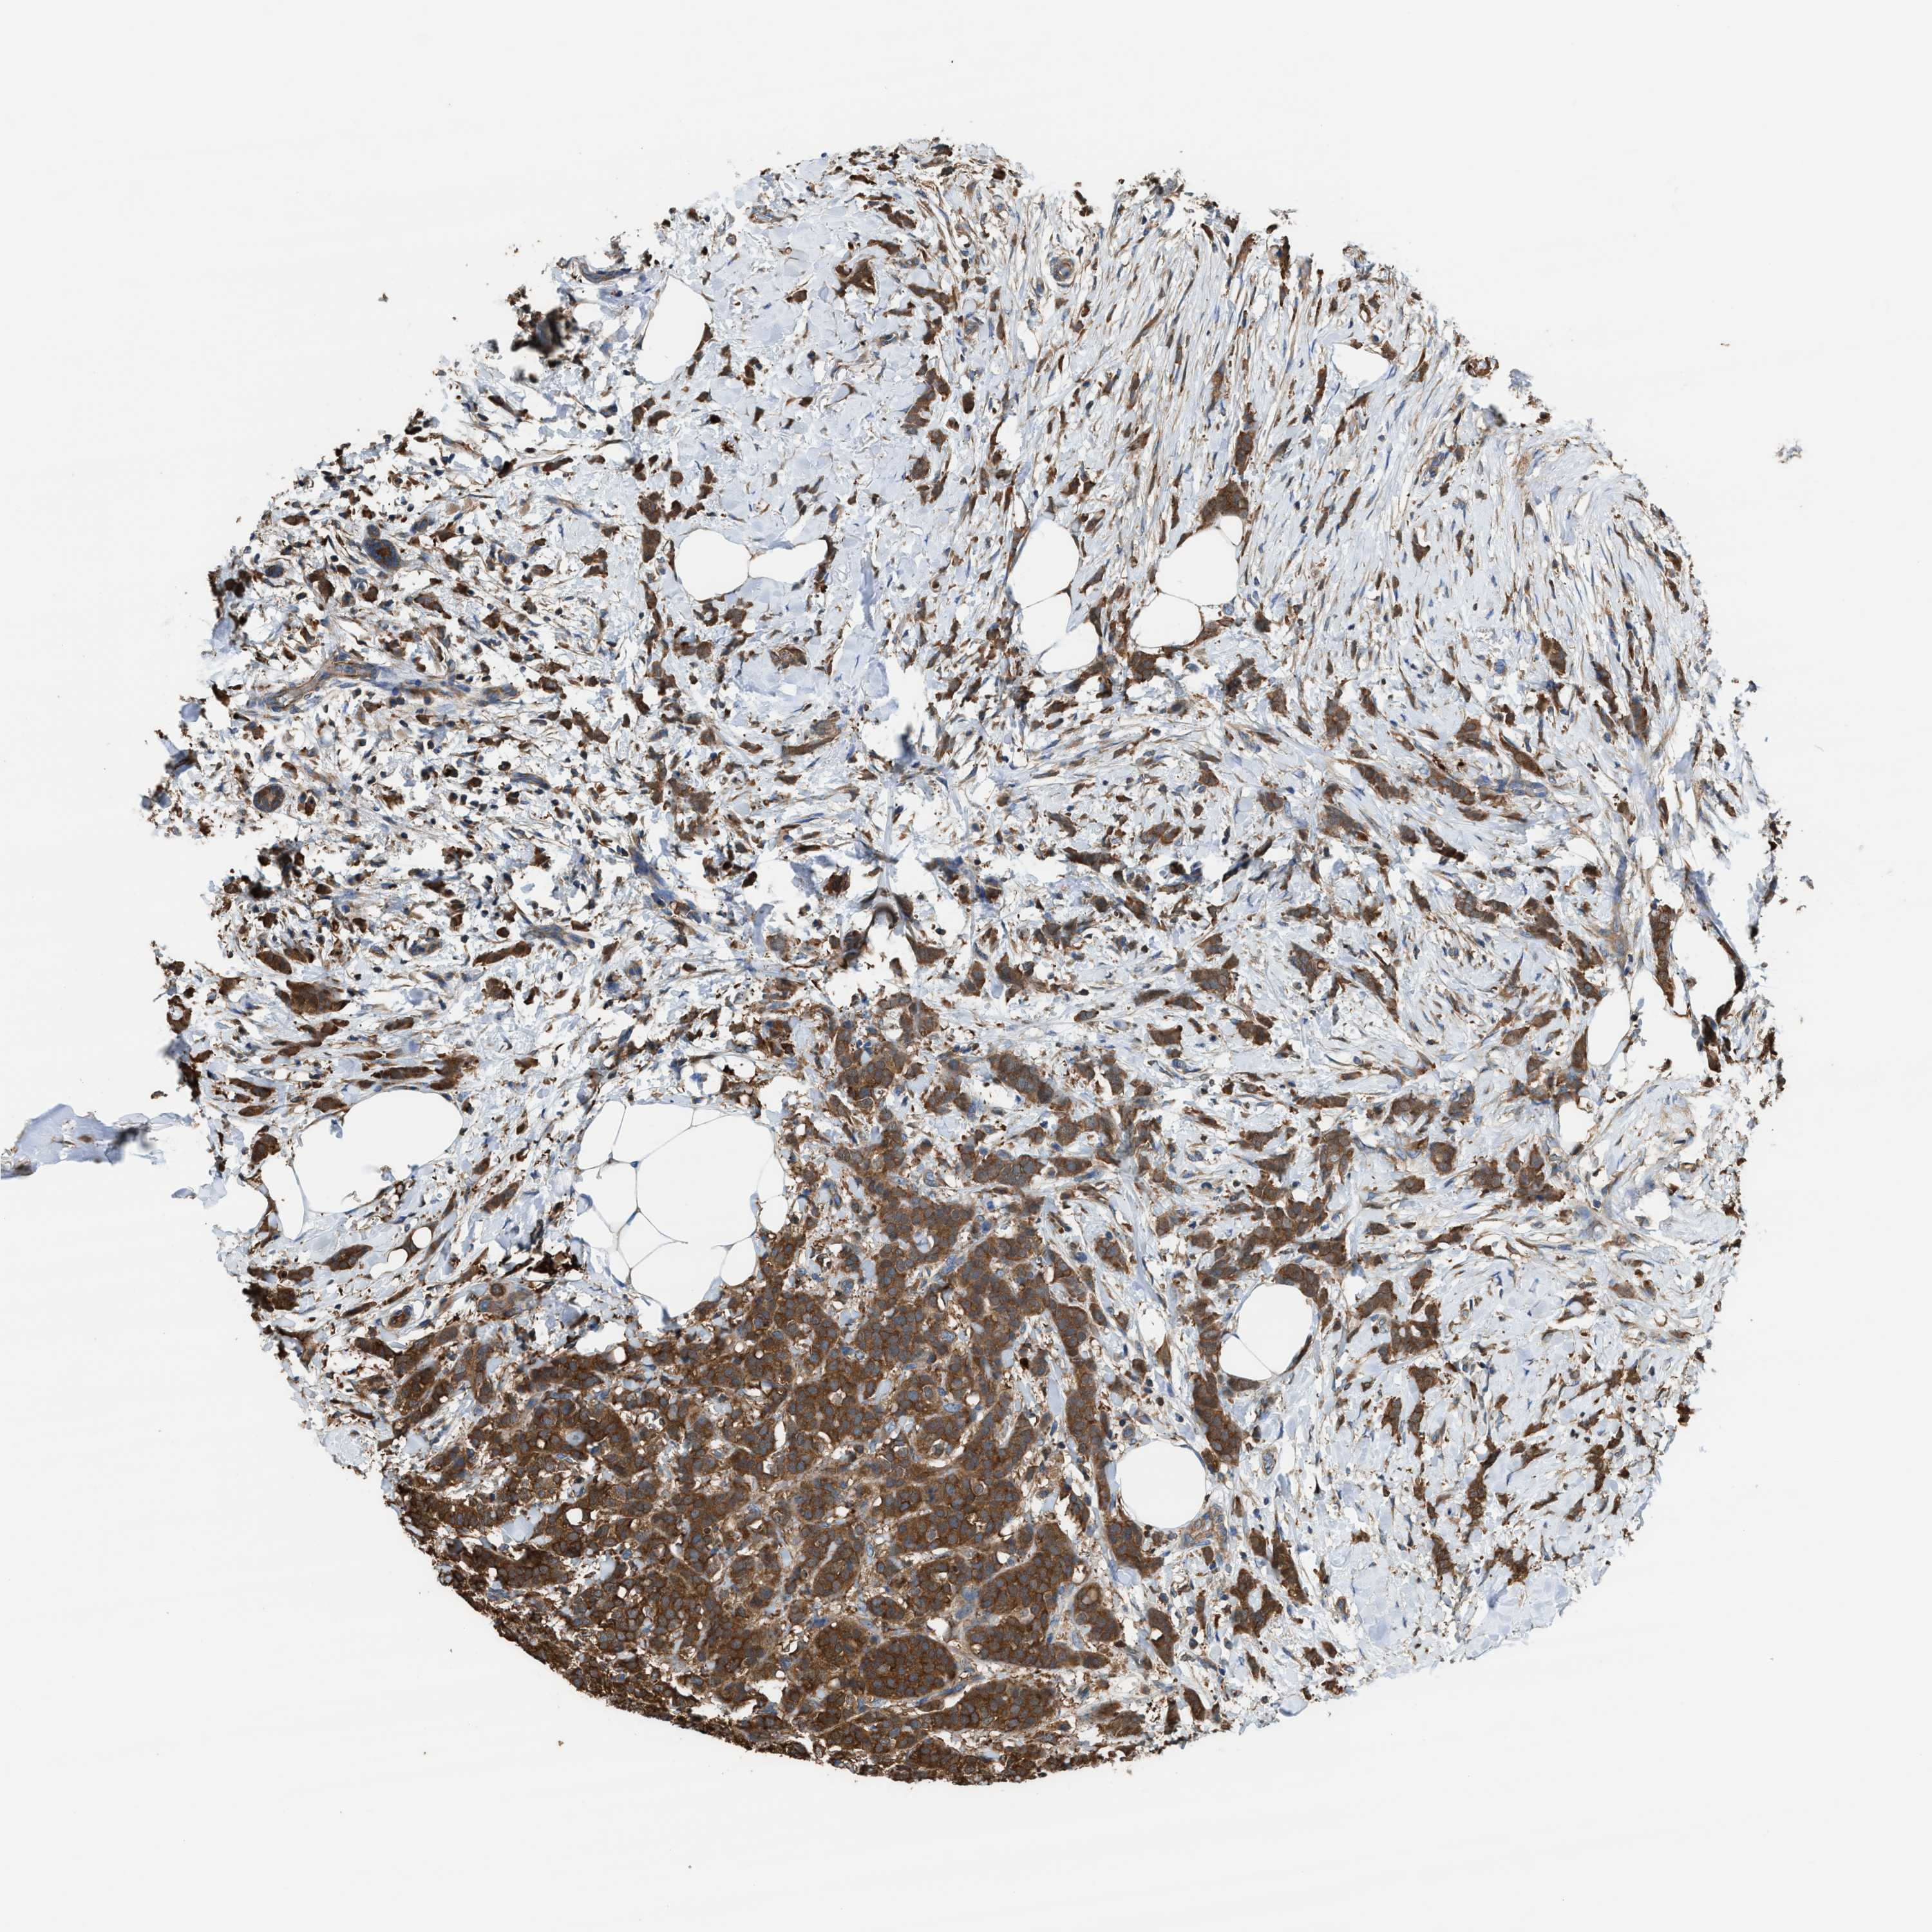

CANCER BREAST CANCER Show tissue menu

BRCA TCGA BRCA VALIDATION PROTEIN EXPRESSION